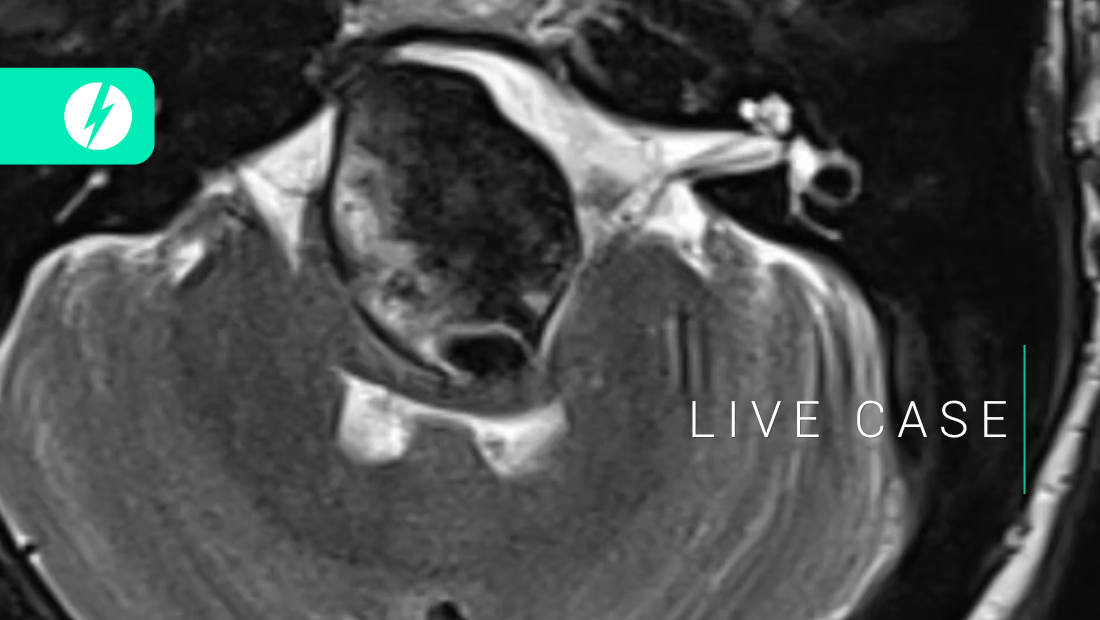

Recanalization of top-of-the basilar aneurysms after simple coiling - SLICE Next Frontiers 2022 - Samantha BIDOO

Extradural giant aneurysms - SLICE Next Frontiers 2022 - Greta REIKONEN